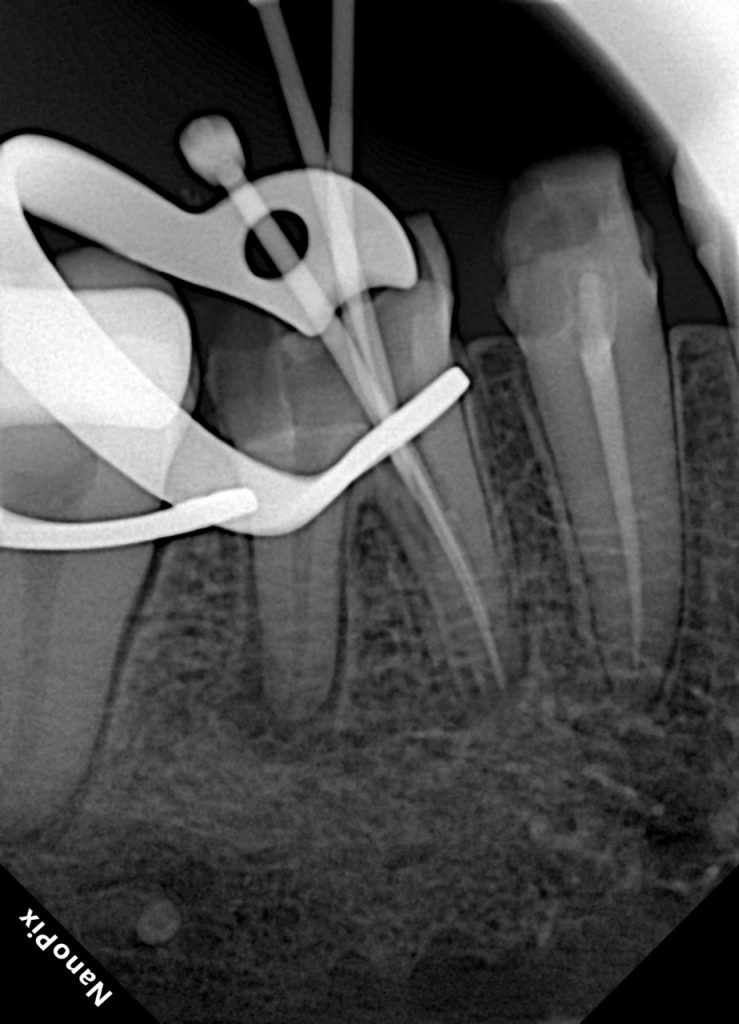

Patient presented with persistent dull pain in a previously treated mandibular molar (Fig 1). Radiograph revealed under-filled canals, apical radiolucency, and a fractured orifice opener lodged in the distal canal. Diagnosis: failed RCT with symptomatic periapical periodontitis.

- Fig 1: Pre-op radiograph showing broken file and defective obturation.